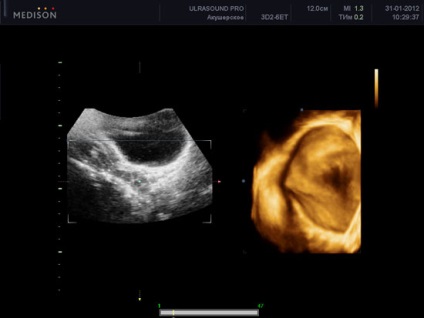

uter ultrasunete 3d

ultrasunete tridimensională a uterului produce indisponibile în proiecție cu ultrasunete convențională și este utilă în evaluarea contururile exterioare ale uterului, și poate detecta anomalii în structura, în special în uter. combinație 3d gidrotubatsii cu ultrasunete poate imagine uter detaliu mare (de exemplu, este foarte valoros atunci când detectarea polipi endometriali). Volumul rezultat al uterului în timpul imaginii tridimensionale pot fi supuse la ultrasunete postprocesare și să obțină mai multe felii în diferite proiecții. O astfel de ultrasunete a uterului este, de asemenea, numit imagistica cu ultrasunete. Astfel, combinația dintre o ecografie bidimensional convențională a uterului și trehmrnogo oferă noi posibilități în imagistică și diagnostic, fiind imposibil de atins folosind ultrasunete conventionale. Cel mai probabil, în viitorul apropiat, astfel de studii vor deveni norma in timpul ecografiei a uterului si apendicelor.